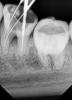

Stomart Опубликовано 4 декабря, 2012 Поделиться Опубликовано 4 декабря, 2012 Снимки делали без инструментов после распломбировки? Такое ощущение, что в медиальных сломали инструмент или заступенили.http://s019.radikal.ru/i601/1212/cc/1def1693eaeb.jpg Ссылка на комментарий

diesel87 Опубликовано 4 декабря, 2012 Автор Поделиться Опубликовано 4 декабря, 2012 Нет, не делал, завтра будет прием, сделаю. Инструменты целые все, контролировал. Ссылка на комментарий

diesel87 Опубликовано 4 декабря, 2012 Автор Поделиться Опубликовано 4 декабря, 2012 За те пол часа что пациентка была на приеме, я успел только распломбировать дистальный, но до верхушки не дошел, упирается. Из медиальных только щечный прошел до апекса, язычный сопротивляется. И если предположить что с межкорневой все в порядке, то завтра буду пробовать дальше проходить и мыться. Ссылка на комментарий